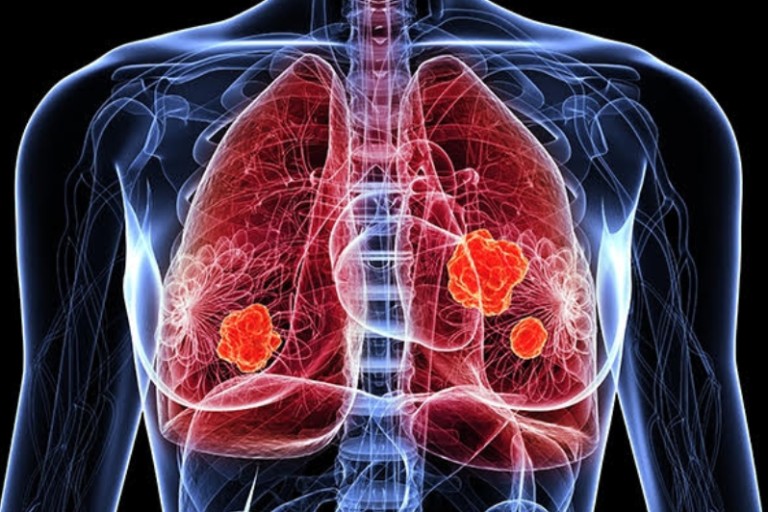

10. 피가 섞인 가래

폐렴이 심각하게 진행되면 가래에 피가 섞여 나올 수 있습니다. 이는 폐 조직이 손상되거나 염증으로 인해 혈관이 파열되어 발생할 수 있으며, 빨리 병원을 찾아 진료를 받는 것이 중요합니다.

폐렴 치료방법

폐렴의 치료 방법은 원인에 따라 다르지만, 일반적으로 다음과 같은 치료가 진행됩니다: